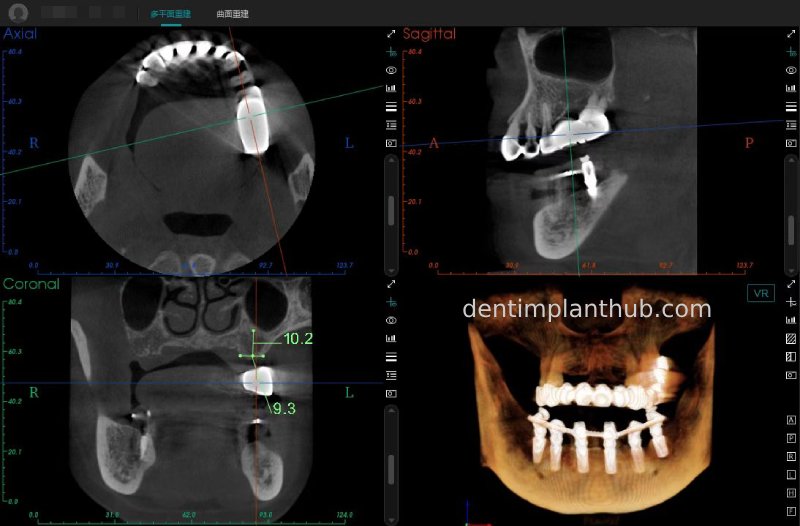

Maxillary condition as shown by CBCT on 13/5/24

16

14

12

22

24

26

Details of implant sites, protocols, implant types, composite abutments, 13.5.24

16, implant model 4810, requires an internal elevation of the maxillary sinus floor and an RC series straight composite abutment;

14, implant model 4812, requires an RC series 15° composite abutment;

12, implant model 4112, requires an RC series 30° composite abutment;

22, implant model 4112, requires an RC series 30° composite abutment;

24, implant model 4812, requiring an RC Series 15° composite abutment;

26, implant model 4810, requiring an internal maxillary sinus floor lift, requiring an RC Series straight composite abutment;